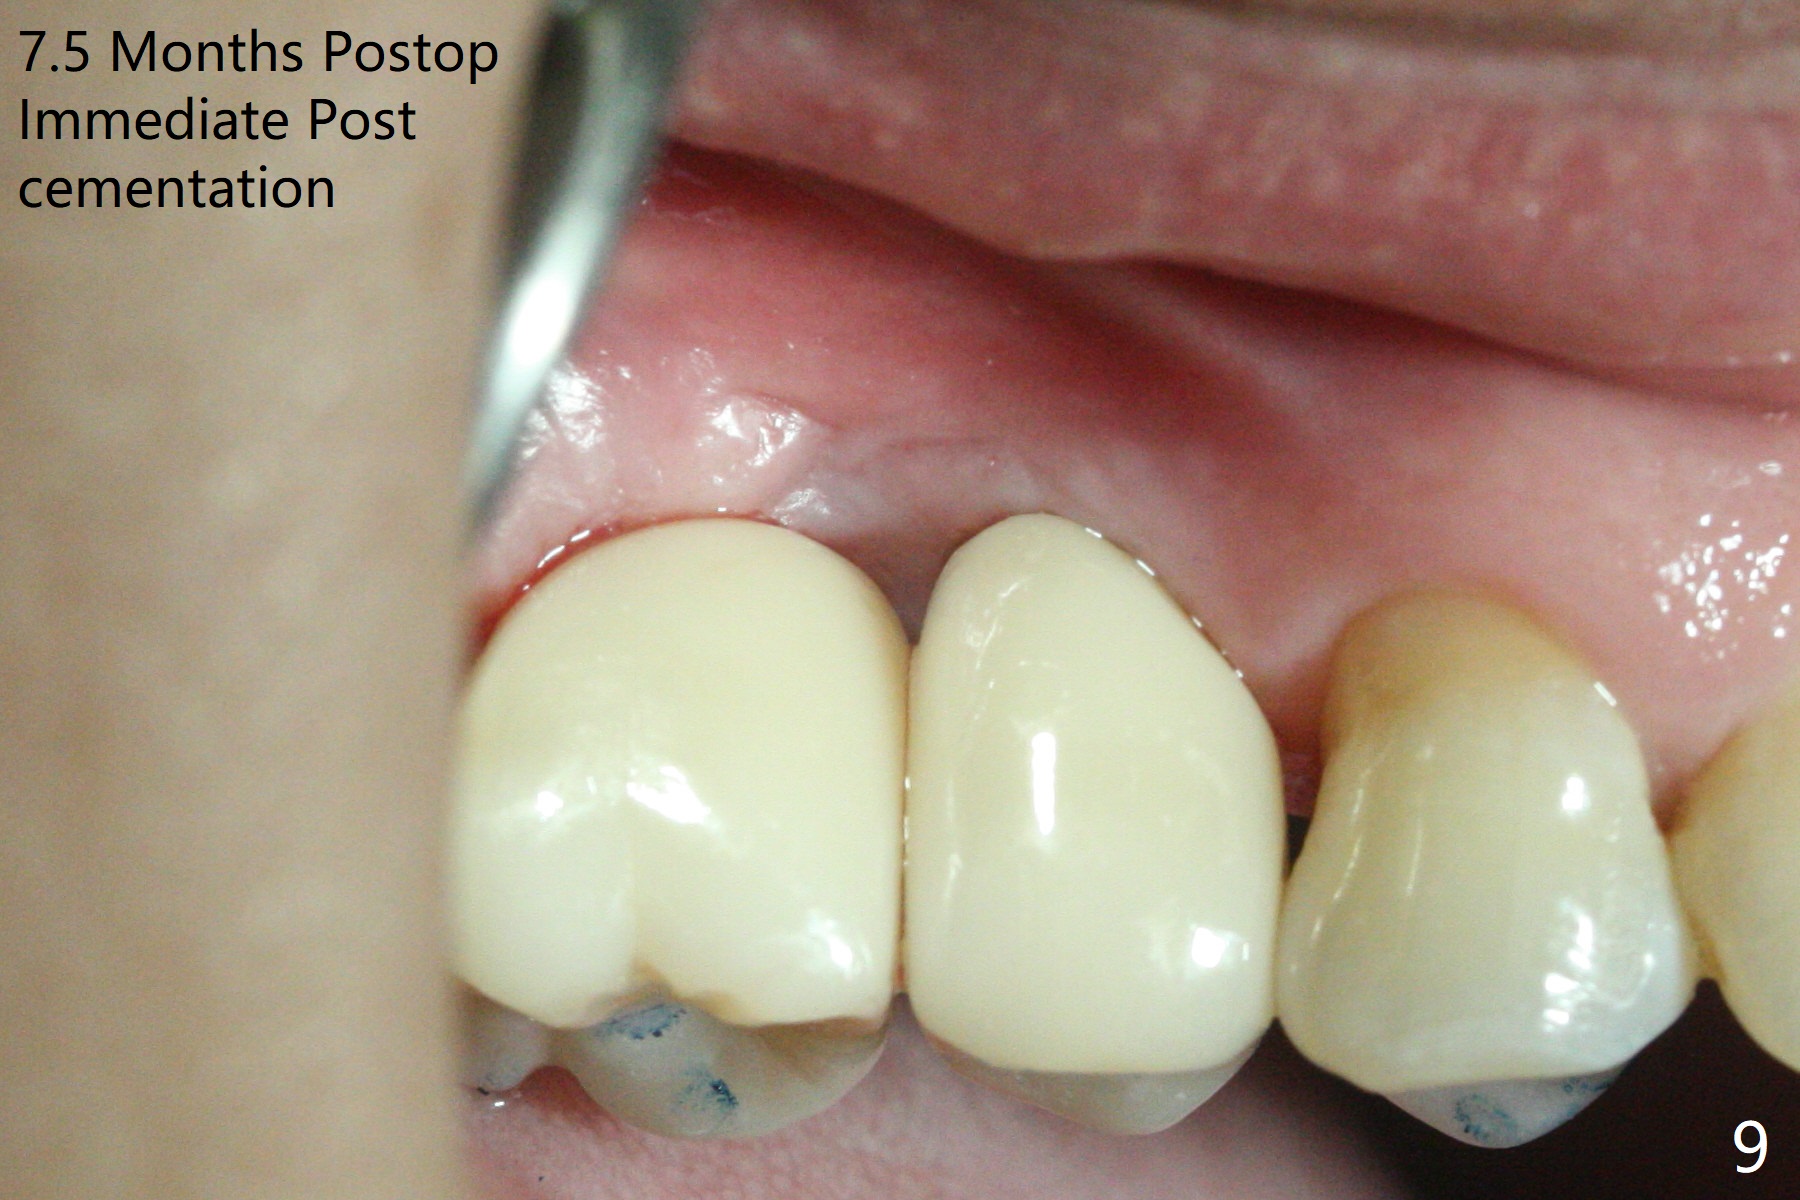

When the tooth #3 with severe buccal gingival recession is extracted and implants are placed at #3 and 4 with guide, sticky bone in 2 large pieces is packed between these implants with a previously large defect in a seemingly secure manner (Fig.1 *). Use of a longer implant at #3 (11.5 mm vs. 10 mm) will reduce the chance of abutment screw loosening in the future. With 2 pieces of PRF membrane coverage, an immediate provisional is fabricated for graft retention (Fig.2,3 P). To stabilize a buccal flap (Fig.2 *, used to be buccal furca gingiva), periodontal dressing is applied later. The buccal socket heals 12 days postop (Fig.4). Apparently new bone forms between the implants 4 months postop (Fig.5). The abutment at #3 may not be completely seated. In fact it is loose, probably related to buccal gingival and gingival cuff erythema 6.5 months postop (Fig.6). Large healing abutments are placed to form the interdental (interimplant) papilla without effect (*). Provisional crowns will be fabricated for the papilla formation. When cemented abutments are placed (Fig.7), papilla formation by manipulation of provisional crowns seems unlikely. Impression is taken. Although there is no implant thread exposure, the buccal plate is concave 7.5 months postop (Fig.8). With special crown design, food impaction should be minimal post cementation (Fig.9,10). There is no bone loss 5.5 months post cementation (Fig.11), while the soft tissue is healthy (data not shown).